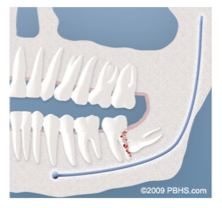

Cyst Formation:

Non-infectious diseases may also arise in association with an impacted wisdom tooth. Cysts are fluid-filled “balloons” inside the jawbone that develop as a result of impacted teeth and slowly expand destroying adjacent jawbone and occasionally teeth. They can be very difficult to treat if your wisdom teeth are not removed in your teenage years. Although rare, tumors can be associated with the delayed removal of wisdom teeth.